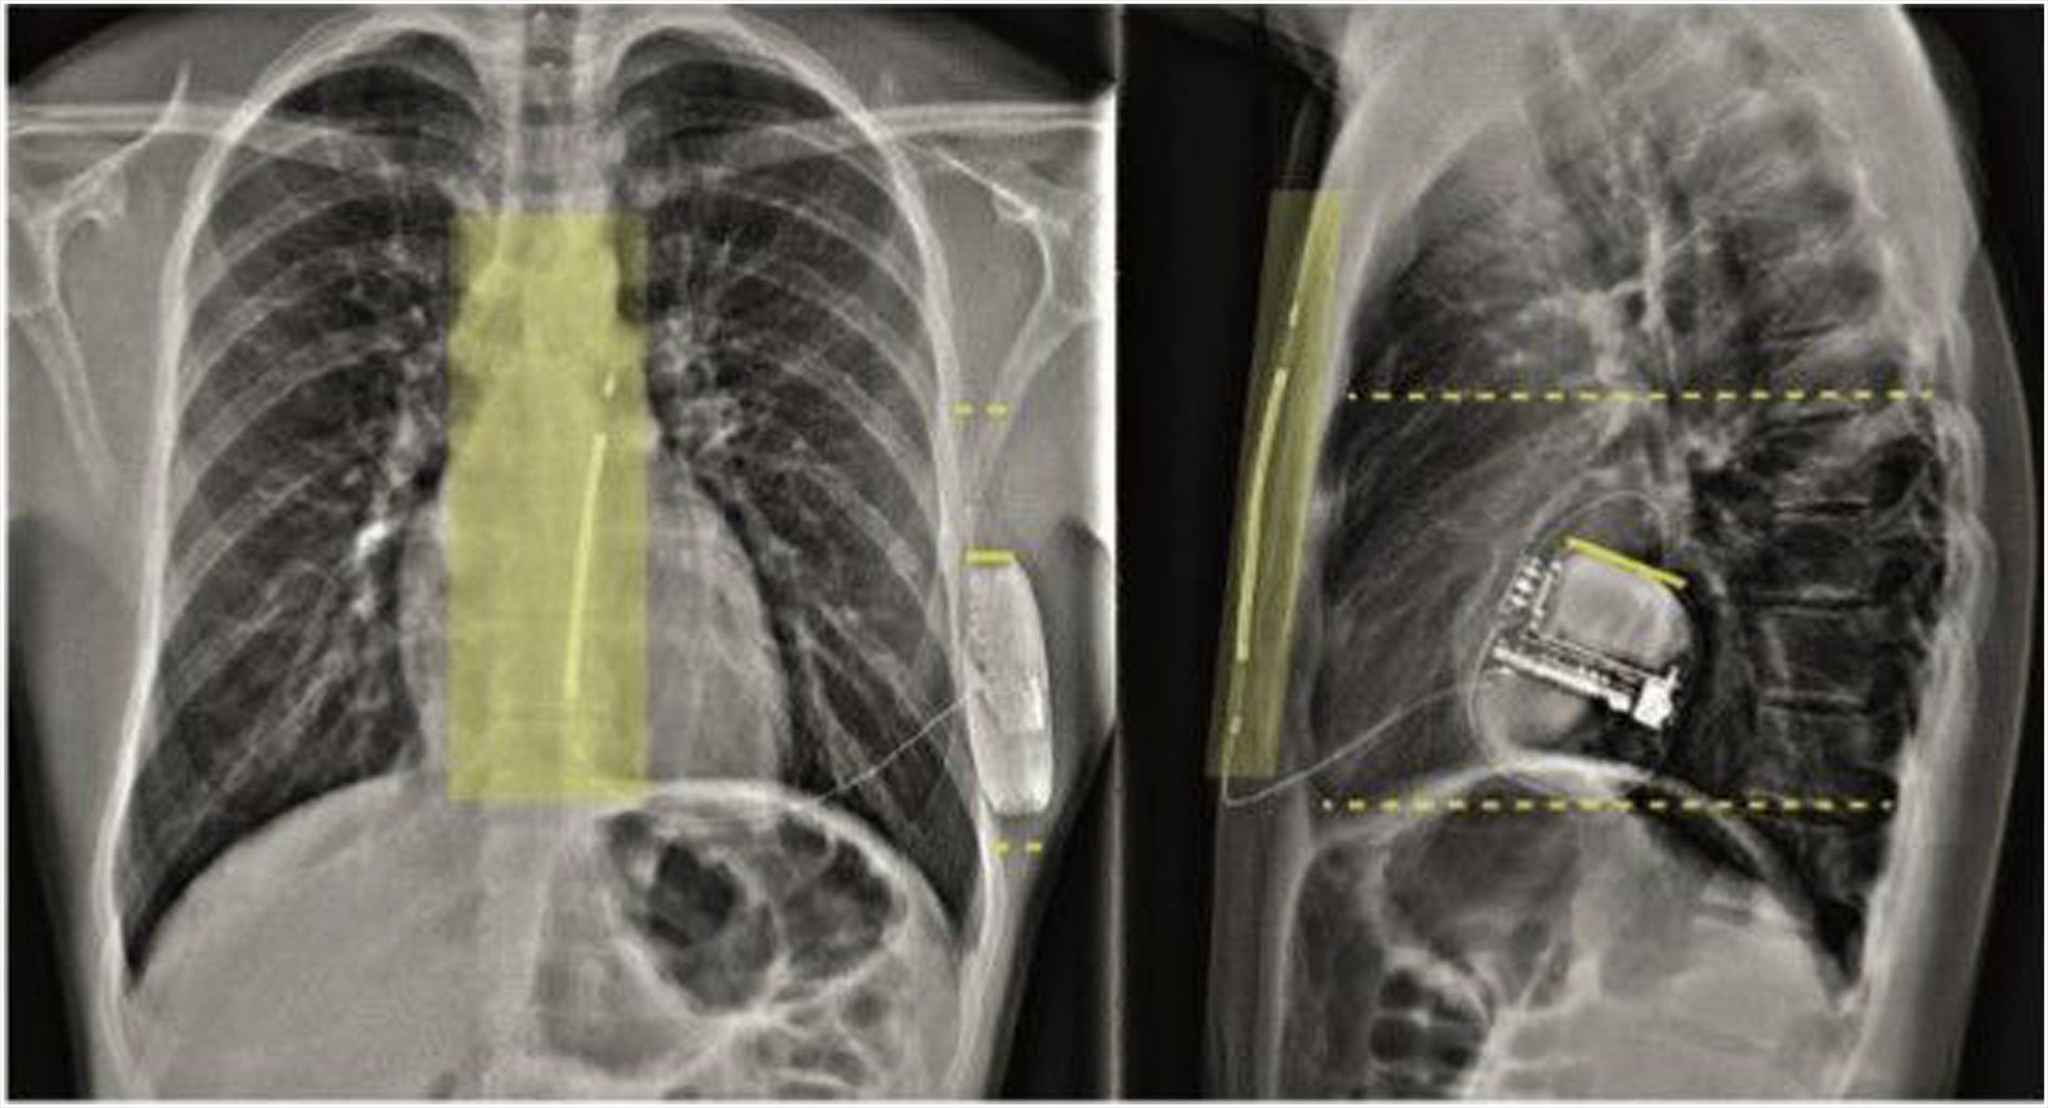

PRAETORIAN Score Summary Figure

*Source Adapted from: 'Predictive Value of the PRAETORIAN Score for Defibrillation Test Success in Patients with Subcutaneous ICD: A Subanalysis of the PRAETORIAN-DFT Trial,' Heart Rhythm.

Generator Positioning DFT Thumbnail

The effect of generator positioning on the defibrillation threshold

Watch the animation about the effect of generator positioning on the defibrillation threshold.